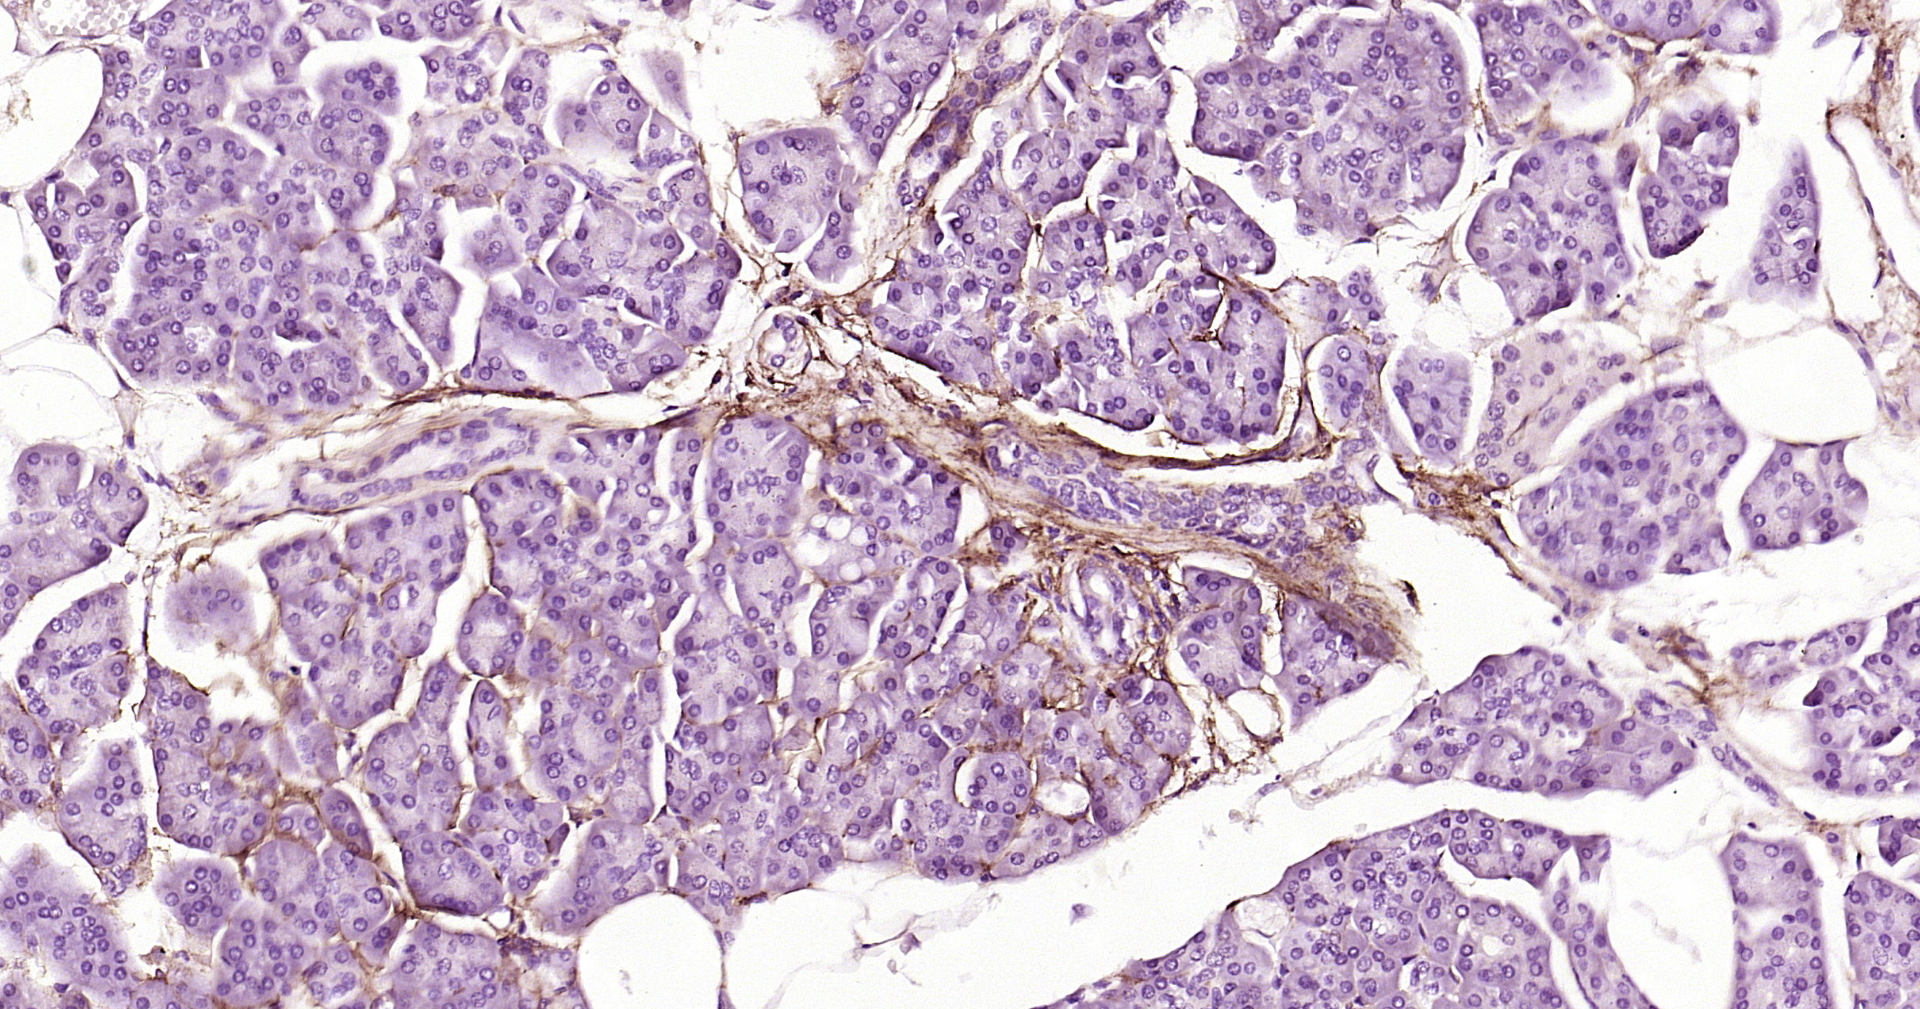

• IHC-P

IHC-P 1:100-500